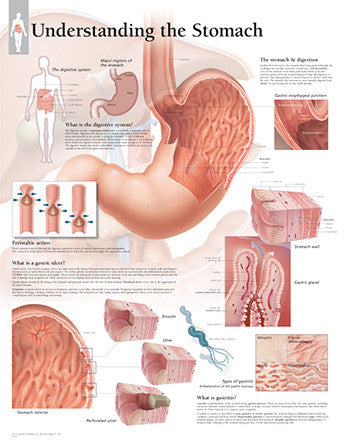

Anatomy

Anatomical models and charts by Body System or Anatomical Region for Nursing, Physical Therapy, and Medical Education.